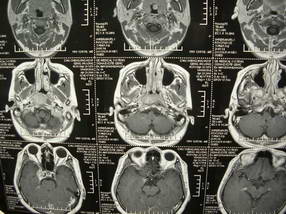

男、30、发现鼻咽部肿瘤侵犯海绵窦,未发现明显淋巴肿。请问国内那家医院治疗鼻咽部肿瘤最好?手术以何种方式为主?病灶可否全部切除?急切期待的大家的帮助。

扫描示鼻咽腔不对称,中度狭窄,右侧咽隐窝消失,局部软组织肿块,鼻咽右侧壁增厚形成肿块,突入鼻咽腔,肿块平扫呈等密度,肿块向深部侵润,右侧翼内外肌受侵,右侧咽旁间隙变窄;向后生长,头长肌界线欠清,向后上生长侵犯同侧颈动脉鞘区。双侧海绵窦增宽,内见软组织影与鼻咽部肿块相连。考虑鼻咽癌。鼻咽癌主要是放射治疗,且效果较好;到当地有治疗设备较大医院治疗即可。